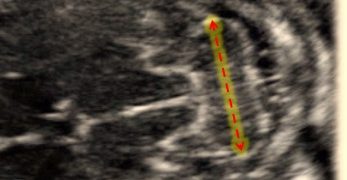

Leggi di piùCari soci, questo mese un nuovo video "How to do", sulla diagnosi ecografica di gravidanza ectopica. Grazie a Danilo Buca! Il video è accessibile ai soli soci SIEOG attraverso questo...